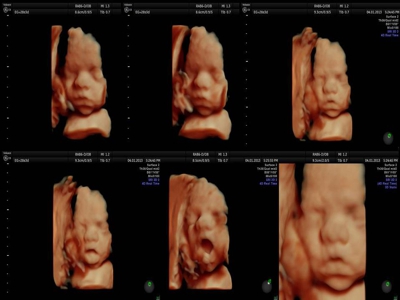

Fotografías de ecografías 4D HD/5D

Haga click sobre las imágenes para ampliar